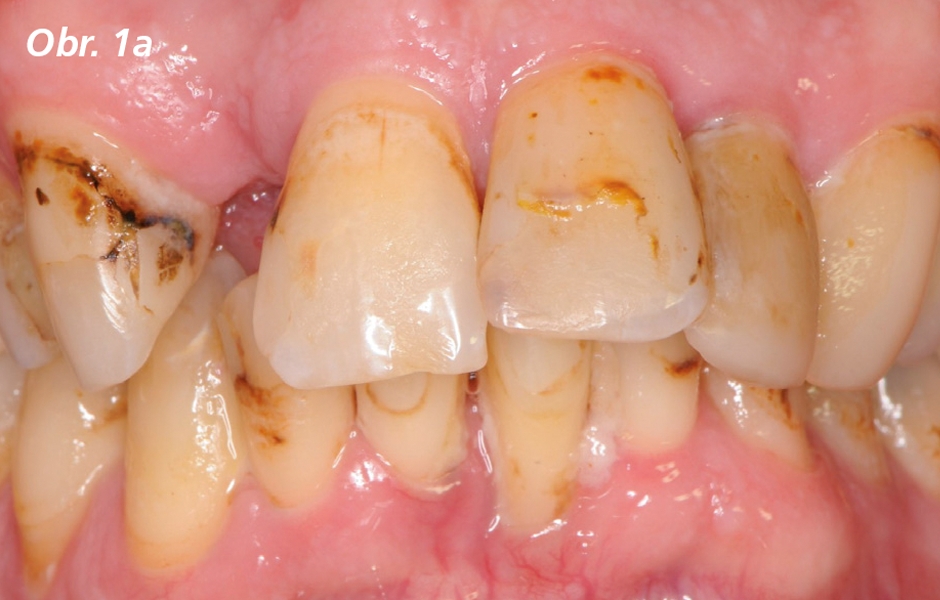

Plně ozubený čtyřicetiletý muž s bezvýznamnou anamnézou se dostavil na protetickou kliniku před extrakcí horního pravého středního řezáku a horního levého středního a postranního řezáku z důvodu parodontitidy a s tím spojené viklavosti (obr. 1a, 1b). Bylo provedeno kompletní klinické a rentgenologické vyšetření ve spolupráci s parodontologem. Před extrakcí horních řezáků byla zhotovena imediátní náhrada. Po extrakcích zubů následovalo socket preservation pomocí kostního alogenního materiálu (Puros Cancellous Particulate Graft, Zimmer Dental, Inc.). Štěpy byly překryty kolagenovými hubkami (CollaPlug, Zimmer Dental, Inc.), přešity (Vicryl 5-0; Ethicon USA, LLC) a byla odevzdána provizorní náhrada. Počáteční hojení po socket preservation bylo příznivé a bez komplikací. Čtyři měsíce po extrakci byly do míst horních postranních řezáků zavedeny dva zubní implantáty (4,5 × 11,5 mm NobelActive RP, Nobel Biocare). Byly překryty krycími šroubky, tkáně byly sešity (Vicryl 5-0; Ethicon US, LLC)a implantátům bylo ponecháno pětiměsíční vhojovací období. Po inkorporaci byla provedena druhá chirurgická fáze. Non-engaging provizorní abutmenty (Conical connection RP 36662; Nobel Biocare) byly zavedeny a zuby ze stávající imediátní náhrady byly v pryskyřičné bázi připojeny k provizorním abutmentům pomocí světlem tuhnoucí akrylové pryskyřice (Unifast LC; GC America). Detailní kontury provizorní náhrady na implantáty byly vytvořeny a upraveny ošetřujícím lékařem v ordinaci. Šroubovaná provizorní náhrada nesená implantáty byla dokončena, vyleštěna a odevzdána v době druhé chirurgické fáze (obr. 2a, 2b).

Výchozí situace před extrakcí horních řezáků